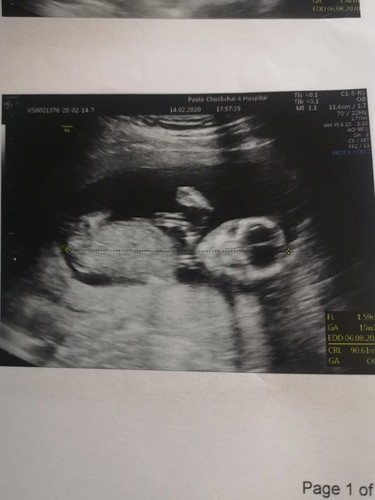

อัพเดทอาการเเท้งคุกคาม15W4Dเข็มที่5 หลังจากที่ฉีดยาทุกสัปดาห์เลือดในสัปดาห์ที่4นี้เป็นสีน้ำตาลอ่อนๆ ออกน้อยลงเป็นหยดๆพอติดเเผ่นอนามัย ไม่ปวดท้องเเม่ไปทำงานได้ปกติเเล้ว พยายามเดินให้น้อยลง หลีกเลี่ยงการขึ้นลงบรรได การนั่งซ้อนมอไซ เเละพักผ่อนให้เพียงพอ ตอนนี้น้องอายุครรภ์15สัปดาห์4วันสัปดาห์นี้น้องดิ้นเก่งมาก โบกมือเเละยิ้มให้พ่อกับเเม่ด้วยคุณหมอดูเพศให้เป็นลูกสาว สมใจพ่อกับเเม่มากๆค่ะ ขอให้ลูกสาวของเเม่เเข็งเเรงโตไวๆ ปลอดภัยจนคลอดออกมาอยู่ให้พ่อกับเเม่กอดในอ้อมอกน๊า❤️